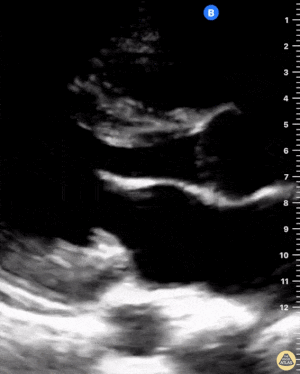

Parasternal uzun aks

Parasternal kısa aks

Sol ventrikül fonksiyonu / kontraktilitesi

Sağ ventrikül disfonksiyonu

Perikardiyal efüzyon (tamponad bulguları eşlik edebilir)